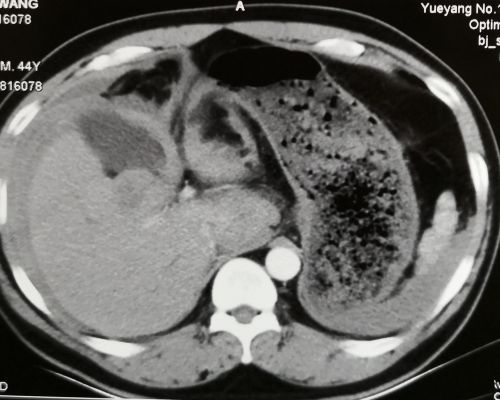

1段和5段的肿瘤。

1段肿瘤破裂、血肿形成。

接到通知后,我立即驾车赶赴岳阳,到达病人身边时已是晚上7点。在仔细查看病人的临床资料并做了体格检查后,我发现病人病情危重:患者男性,44岁,病史较为典型,由慢性乙肝发展为肝硬化,再转化为原发性肝癌,突发肝癌破裂大出血,虽经介入止血治疗,但病人腹腔内有大量积血,估计超过2000ml,血红蛋白仍较低,不排除仍有出血。肝内肿瘤位于1段和5段,1段肿瘤已破裂,周围形成血肿,且位置深,处理有难度。

晚上8点手术开始,探查发现腹腔内积血和血凝块2500ml,清除后发现肝脏情况和术前分析相符。打开小网膜囊,套通肝十二指肠韧带,切除胆囊,显露1段和5段的肿瘤。阻断第一肝门,先完整切除1段肿瘤,再剥除5段肿瘤,彻底止血。这两步顺利完成后,留置4根引流管,用5-Fu+奥沙利铂方案43℃行腹腔热灌注化疗60分钟。手术过程顺利,达到了术前设定的较为理想的目标,输血浓缩RBC6U,血浆600ml,历时5小时,术毕已是次日凌晨1时。